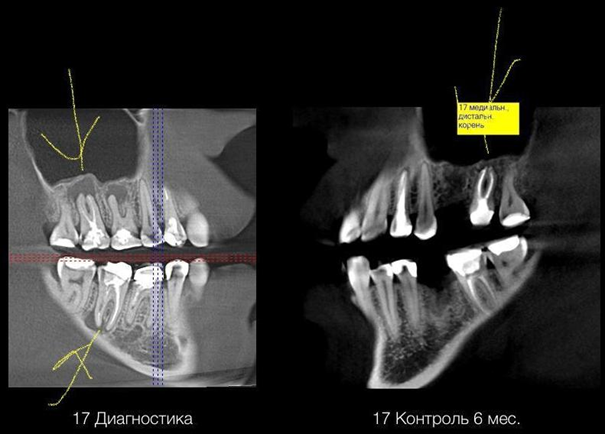

На снимке стрелка показывает на большой очаг разрежения в области верхнего правого седьмого зуба, где кости уже, по сути, нет. Это киста, заполненная грануляционной тканью (незрелый рубец), продуктами жизнедеятельности и мёртвыми бактериями. Она постепенно растёт, разрушая окружающие ткани. Объём гнойного содержимого уже настолько велик, что скоро может прорваться в полость гайморовой пазухи со всеми последствиями в виде одонтогенного гайморита и распространением инфекции. Как вы видите, шестой зуб пришлось убрать из-за значительного разрушения, но седьмой удалось спасти. Был весьма впечатляющий момент, когда после прохождения канала до его верхушки, из канала ручейком начало сливаться содержимое кисты. Девушка сделала круглые глаза и удивлённо сказала, что у неё будто исчезло ощущение постоянного давления, к которому она привыкла. В итоге после устранения очага инфекции кость тоже восстановилась в течение полугода.

На снимке это выглядит как пустое округлое пространство. Вот, например, снимки той девушки, про которую я говорил в самом начале. Возле корней нижних и верхних зубов мы видим очаги разрежения, будто пустые. Это как раз кисты, заполненные жидкостью. Кость в этом участке из-за постоянного давления распалась.